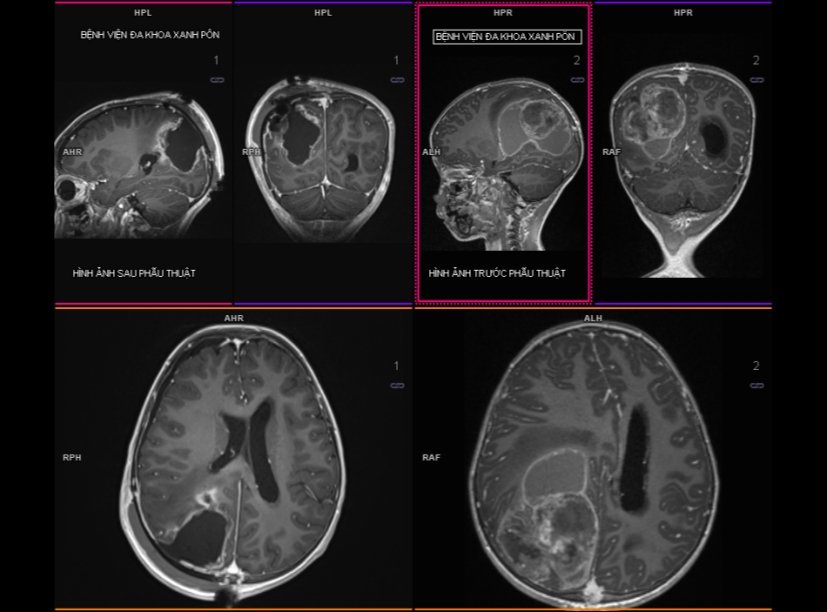

Hình ảnh dưới đây là một trường hợp u não của một bệnh nhi 5 tuổi, đến viện với triệu chứng nôn kéo dài. Bệnh nhân đã được phẫu thuật cấp cứu vì có tình trạng chảy máu trong u. Kết quả giải phẫu bệnh ghi nhận là Atypical teratoid/Rhabdoid tumor.